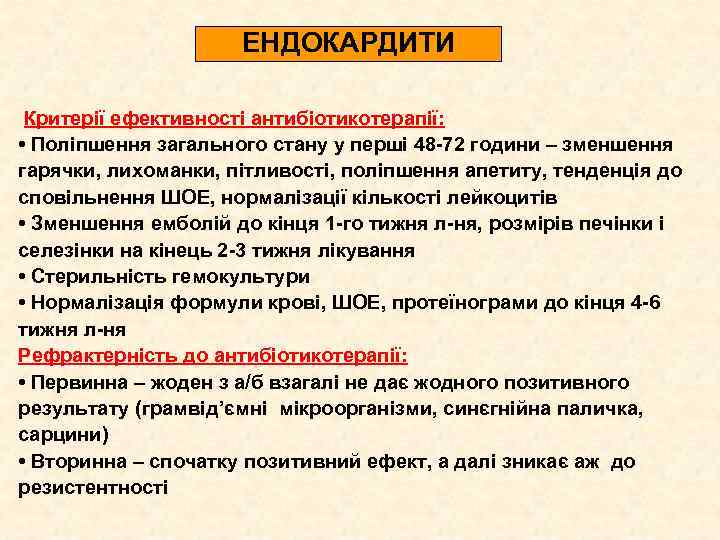

ЕНДОКАРДИТИ Критерії ефективності антибіотикотерапії: • Поліпшення загального стану у перші 48 -72 години – зменшення гарячки, лихоманки, пітливості, поліпшення апетиту, тенденція до сповільнення ШОЕ, нормалізації кількості лейкоцитів • Зменшення емболій до кінця 1 -го тижня л-ня, розмірів печінки і селезінки на кінець 2 -3 тижня лікування • Стерильність гемокультури • Нормалізація формули крові, ШОЕ, протеїнограми до кінця 4 -6 тижня л-ня Рефрактерність до антибіотикотерапії: • Первинна – жоден з а/б взагалі не дає жодного позитивного результату (грамвід’ємні мікроорганізми, синєгнійна паличка, сарцини) • Вторинна – спочатку позитивний ефект, а далі зникає аж до резистентності